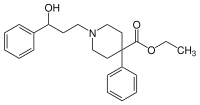

4-Phenylpiperidines

Pethidines (meperidines)

Structures